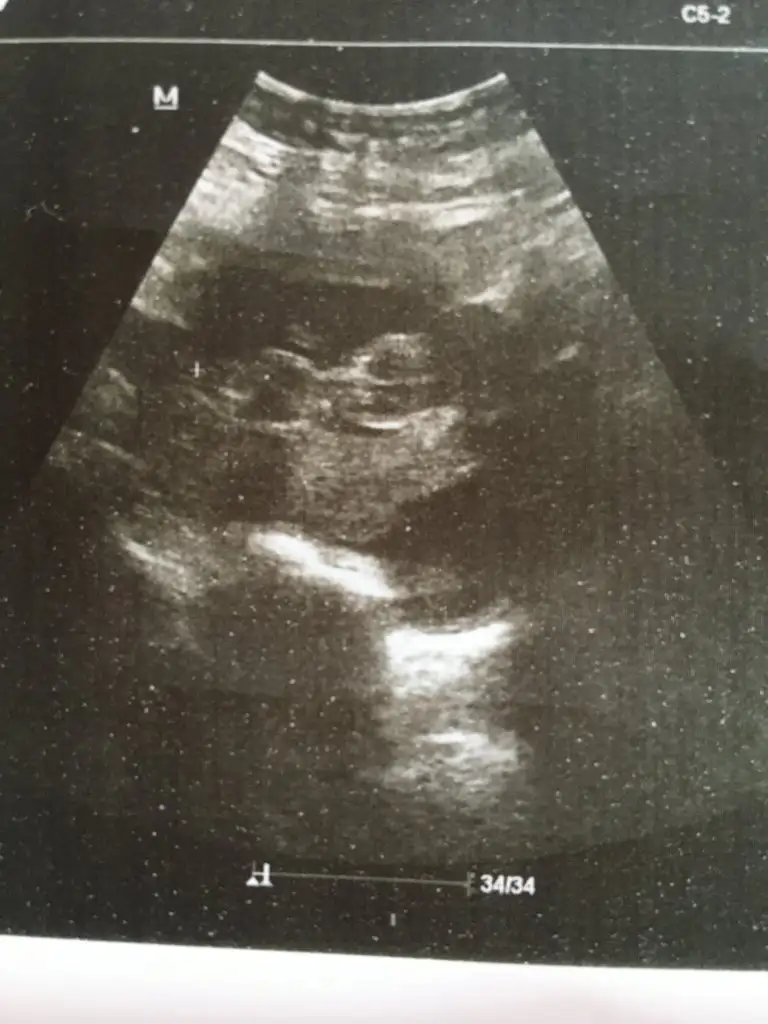

Tahminim kızdı dogum yaklaşmıştır dogru ise tahminim anketimi oylarmısınız

Merhaba dogum yaptınızmıkız gibi geldi ama emin olamadım yakınlaşınca usg puslanıyor 12+ yada 13 haftasında tekrar paylaşın yada başka usg varsa paylaşın

Kız gibiKaç kez paylaşmışım

YaKız gibi

Emin olmamakla birlikte sanki kız nub tarafı çok karanlık başka usg varmı paylaşınEki Görüntüle 2590346 Eki Görüntüle 2590346 Çok belirgin değil ama 12.hafta usg mizIkra meyra Eki Görüntüle 2590346

10+4 te ki vardı ona da kız demiştinizEmin olmamakla birlikte sanki kız nub tarafı çok karanlık başka usg varmı paylaşın